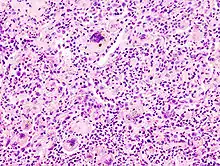

Severe aspiration pneumonia

Microscopic image of aspiration pneumonia in an elderly person with a neurologic illness. Note foreign-body giant cell reaction.